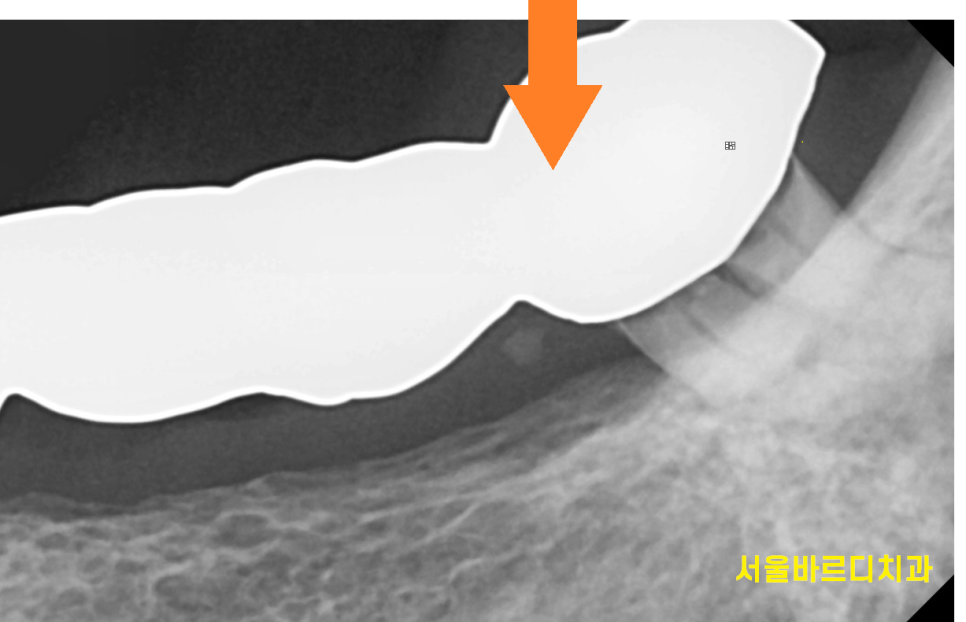

아래 치아도 염증도 있고

목 부분이 부러져 건들 건들거리는 상황

230728 부러져서 흔들거리는 상황

목이 부러져서 건들거리는 왼쪽 아래가

제일 불편하다고 하셔서